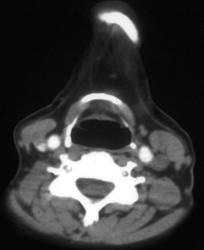

Diagnosis

Pulmonary Embolism